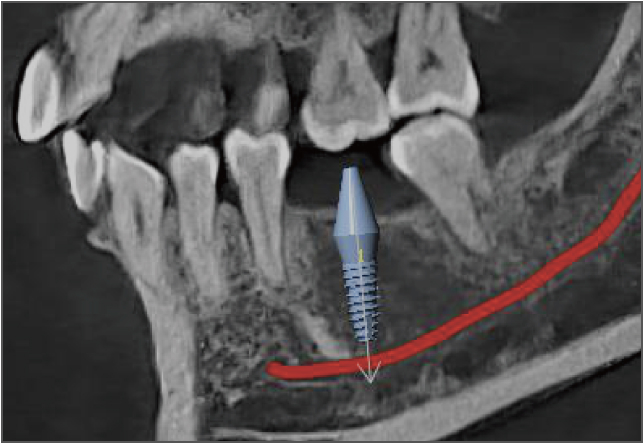

• lamtau 模擬種植

模擬種植